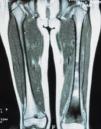

Fig. 3.--RMN en la que se aprecia tumoración en el tercio distal de ambos fémures con permeación de la cortical.

Fig. 3.--MRI showing tumors in the lower third of both femurs and infiltration of the cortical layer.